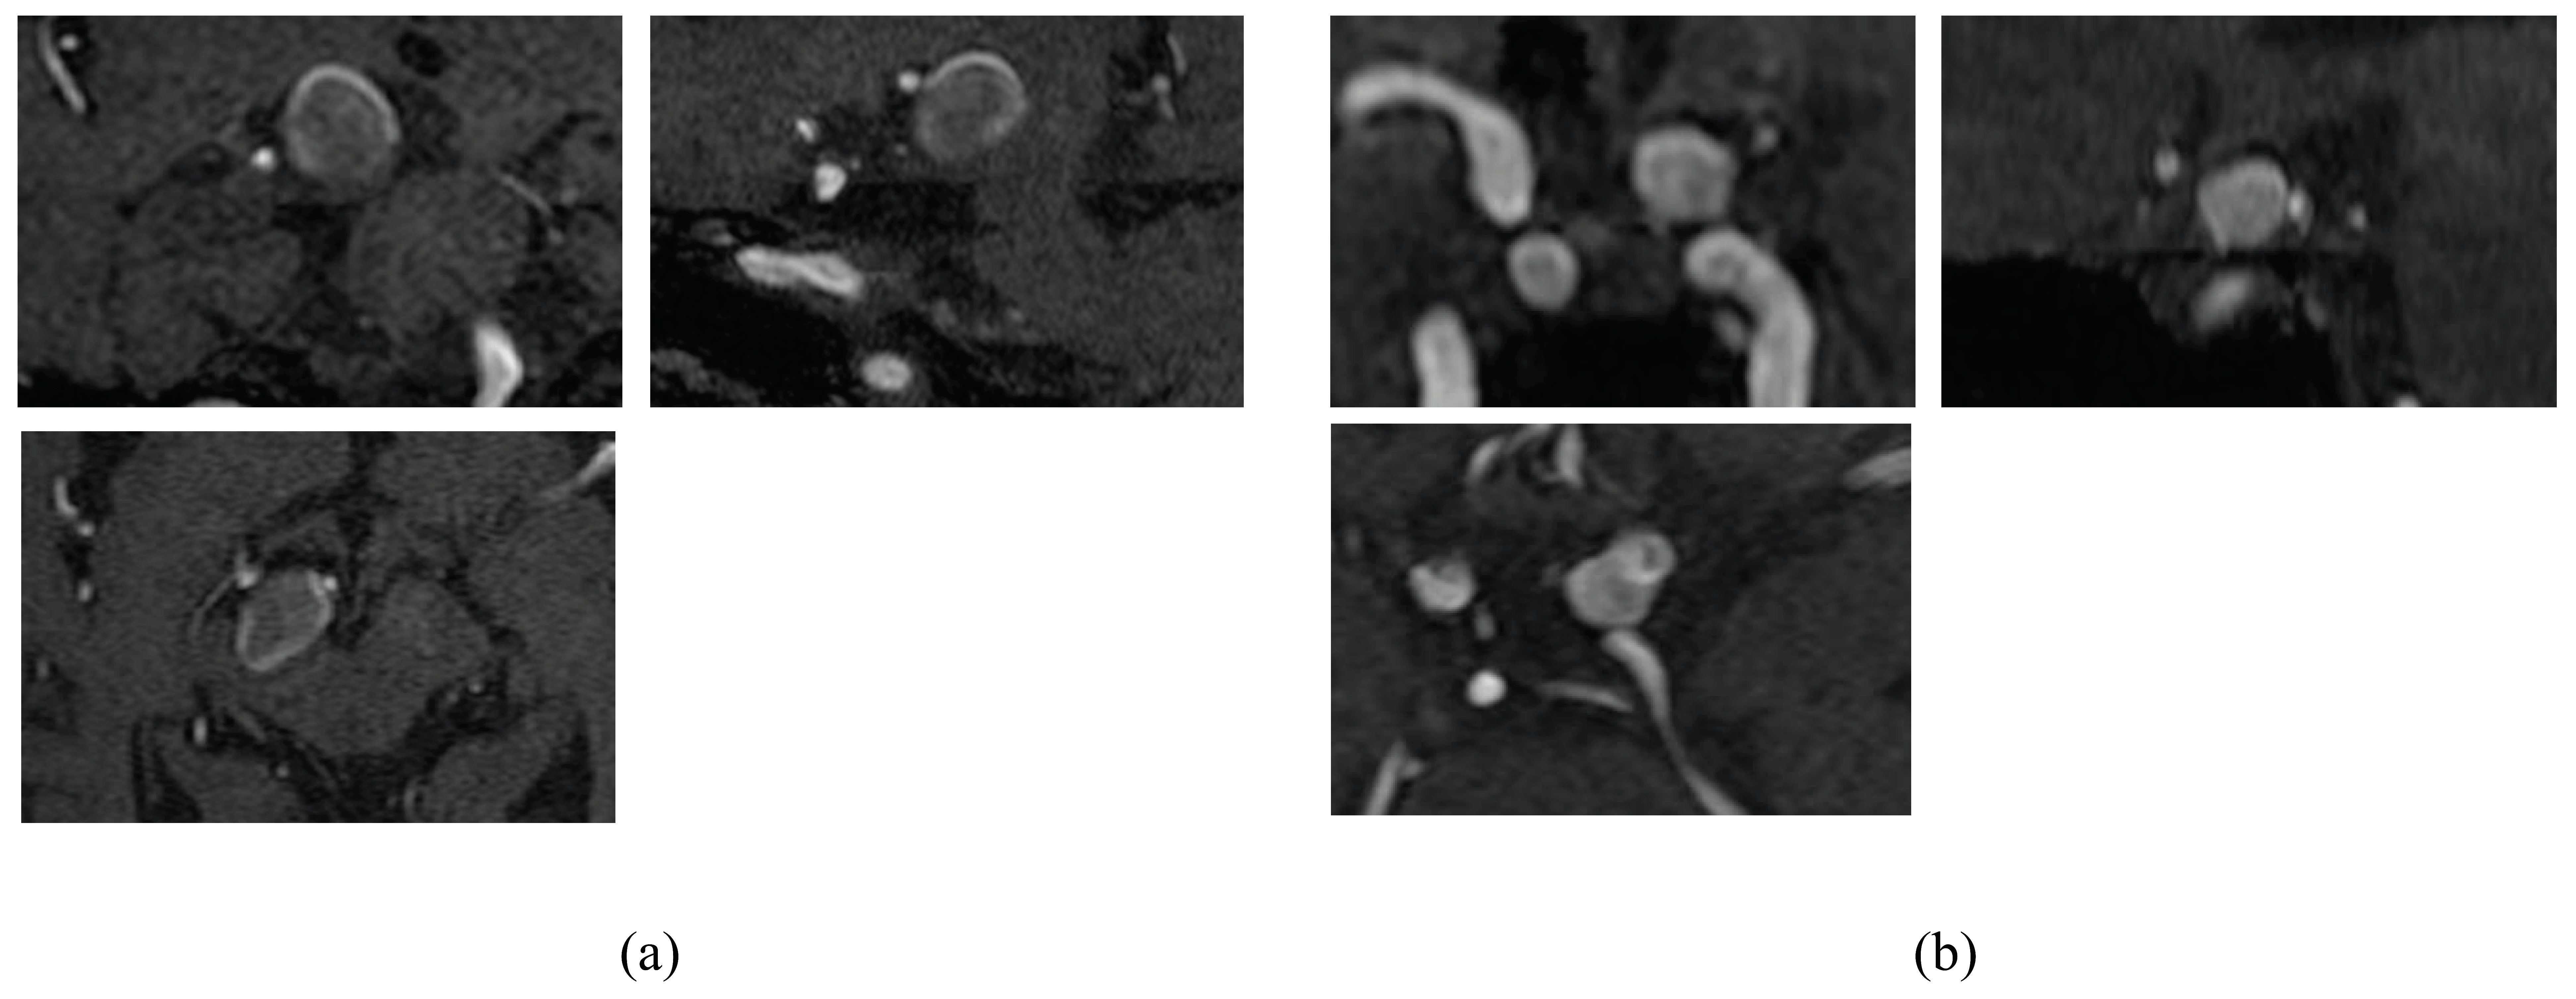

2. Materials and Methods

2.1. Patient Data

2.2. Calculation of Radiomics Image Features